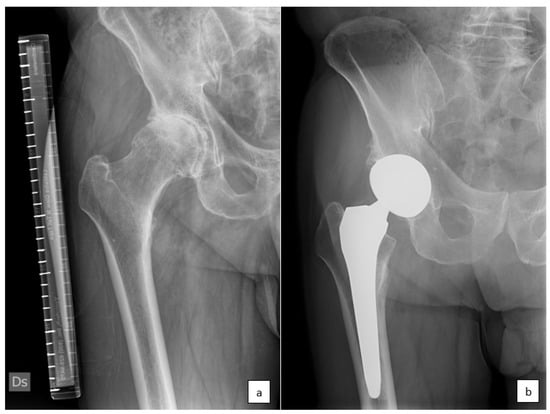

Figure 1.

(a) Osteoarthritis of the right hip, grade III by Kelgren and Lawrence. (b) The same patient with right hip replacement at 7 years of follow-up. The hip stem appears to be stably fixed, with evidence of spot welds, mild signs of stress shielding on the greater trochanteric area, and no signs of subsidence.